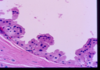

What is this?

Breast abscess: Fibrous capsule with inflammatory infiltrates